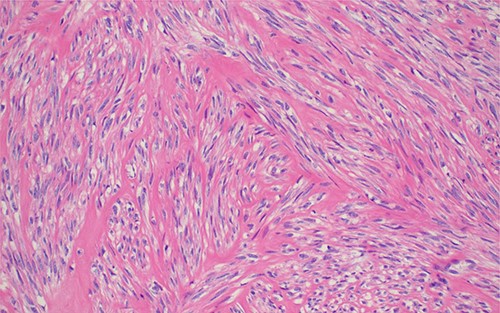

Photomicroscopy of the lesion highlighting positive immune-reactivity of the tumor cells with desmin immunostaining; IHC stained section 200× original magnification.

The definitive diagnosis is achieved by histology. Microscopically, leiomyoma consists of monomorphic spindle cells with blunt-ended nuclei, arranged in interlacing fascicles, without atypia, mitosis or necrosis [4, 6, 7].

Due to rarity of this entity, two different high institute pathology laboratories were used to confirm the diagnosis.